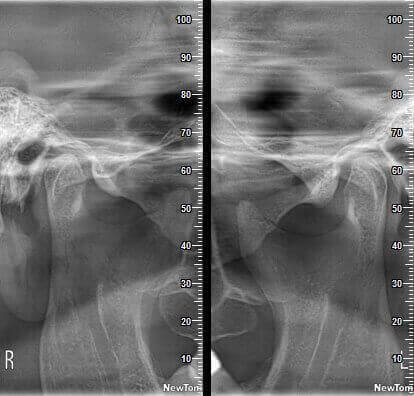

КОМПЛЕКСНЫЙ ГИБРИДНЫЙ КЛКТ ДЛЯ 2D/3D ВИЗУАЛИЗАЦИИ. ИЗОБРАЖЕНИЯ В ВЫСОКОМ РАЗРЕШЕНИИ С ЗАХВАТОМ МЕЛЬЧАЙШИХ ДЕТАЛЕЙ

GIANO HR – универсальное обновляемое устройство от NewTom для всех задач, связанных с радиографией. Благодаря полному диапазону опций 2D и 3D исследования для стоматологии оно предлагает множество особых трехмерных обследований для челюстно-лицевой хирургии, оториноларингологии и осмотра шейного отдела позвоночника. Визуализация только наивысшего качества с технологиями и опытом NewTom

NewTom GiANO HR новейшая модель была официально представлена на международном конгрессе радиологов ECR 2018 в марте в Вене. Благодаря обновленным системам механики и запатентованным механизмам работы аппарат отличается от своих сверстников Высочайшим качеством получаемых изображений, как 2D, так и 3D. Лучшее качество снимков и мы отвечаем за это! Этот аппарат заменит три аппарата! Панорамный аппарат, цефалометрическая приставка и конусно-лучевая компьютерная томография интегрированы в единую платформу. В комплекте детектор для выполнения 3D исследований с захватом области 13х16 см, Сьемный 2D CMOS детектор для выполнения панорамных исследований, и ТРГ.